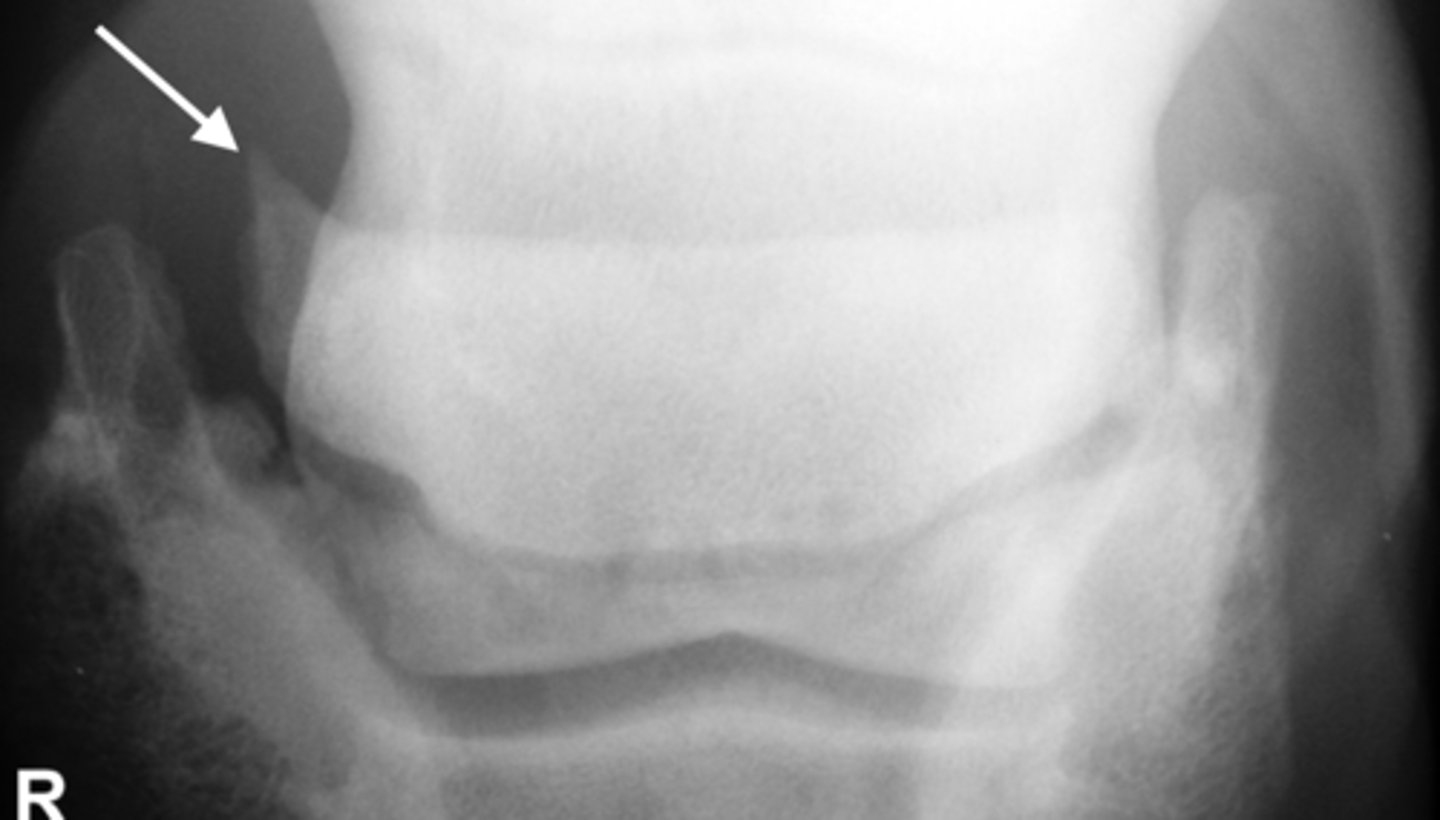

Erosive

Erosive or non erosive?

Non-erosive